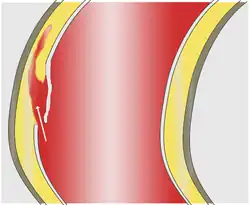

Aneurisma é a dilatação anormal de um vaso sanguíneo causada pelo enfraquecimento das paredes do vaso, por trauma ou por doença vascular.[1] Pode ocorrer basicamente em qualquer vaso sanguíneo. É muito comum na população em geral, raramente causando sintomas ou problemas graves. Seu perigo está no fato de poder romper-se, resultando em hemorragia ou isquemia dos tecidos irrigados pela artéria atingida, sendo que a gravidade do dano depende da área irrigada pelo vaso afetado. O risco é maior caso o paciente seja fumante[2] ou tenha histórico familiar de doenças vasculares, problemas renais ou pressão alta.[3]

Um aneurisma cerebral é uma patologia provocada pela dilatação segmentar, em formato variável, de um vaso na massa encefálica (encéfalo), geralmente arterial ou, menos frequentemente, venoso, como por exemplo, o raro aneurisma da veia de Galeno.

Quando a área deformada do vaso toma forma esférica, dá-se o nome de aneurisma saciforme ou sacular (de saco), ou quando tem forma alongada através do eixo principal do vaso, aneurisma fusiforme (de fuso).

O aneurisma sacular se desenvolve na parede de artérias com defeitos congênitos decorrente do aumento do fluxo sanguíneo ou pressão arterial, entre outras causas. É comum esses aneurismas se romperem, provocando hemorragia cerebral, causando até um acidente vascular encefálico hemorrágico (mais conhecido como derrame cerebral). É bastante perigoso e acarreta hemorragia com frequência.

Rompimento do aneurisma cerebral

A consequência do rompimento do aneurisma cerebral é um fenômeno patológico, chamado de acidente vascular cerebral hemorrágico - ou AVC ou AVCH ("derrame", na linguagem popular). Os aneurismas, na maioria dos casos, não geram qualquer tipo de sintoma até a sua ruptura e sangramento. Menos frequentemente, o aneurisma pode crescer, comprimindo estruturas como nervos causando paralisia como acontece frequentemente com a queda súbita dede uma pálpebra, indicando possibilidade de ruptura. Existem outras causas de AVCH e o sangramento por aneurisma não é a causa mais frequente. Pode haver sangramento para dentro do tecido cerebral (menos comum); hemorragia subaracnoide, HSA, também conhecida como hemorragia meníngea espontânea ou para dentro dos ventrículos cerebrais, podendo provocar hidrocefalia. A ocorrência da hemorragia é em geral súbita, repentina, com duração dos sintomas e sua intensidade variáveis, passível de produzir alterações da consciência, da motricidade, da palavra, entre outras.A cefaleia súbita, descrita como a dor de cabeça mais forte que o indivíduo sente em toda a sua vida, acompanhada de desmaio (perda da consciência) e vômitos são a tríade de sintomas mais comuns na HSA.